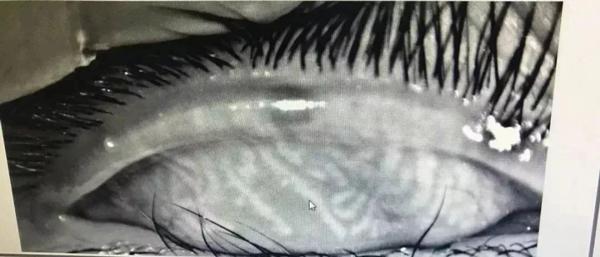

Các tuyến mebomius của cậu bé Tiểu Tân bị rối loạn.

Có khoảng 32 tuyến meibomius trên mí mắt của người bình thường, được sắp xếp thành các đường thẳng đứng song song, tiết ra dầu để làm ẩm nhãn cầu. Tuy nhiên, với Tiểu Tân, các tuyến meibomius của cậu bé đã bị "xoắn" thành một mạng lưới, không còn rõ ràng, giống như mắt của người trung niên và người cao tuổi nhưng ở mức độ còn tồi tệ hơn. Vì vậy, mắt cậu bé mới bị đau nhói, nóng rát và không thể mở nổi mắt. Điều đáng buồn hơn nữa khi bác sĩ nói rằng khó có thể khôi phục hoàn toàn chức năng tuyến meibomius của Tiểu Tân.